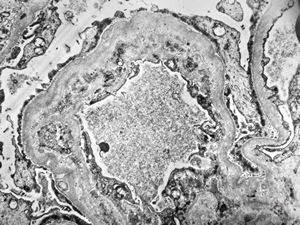

F,14y. | Alport syndrome - split and laminated, thick/thin basement membranes